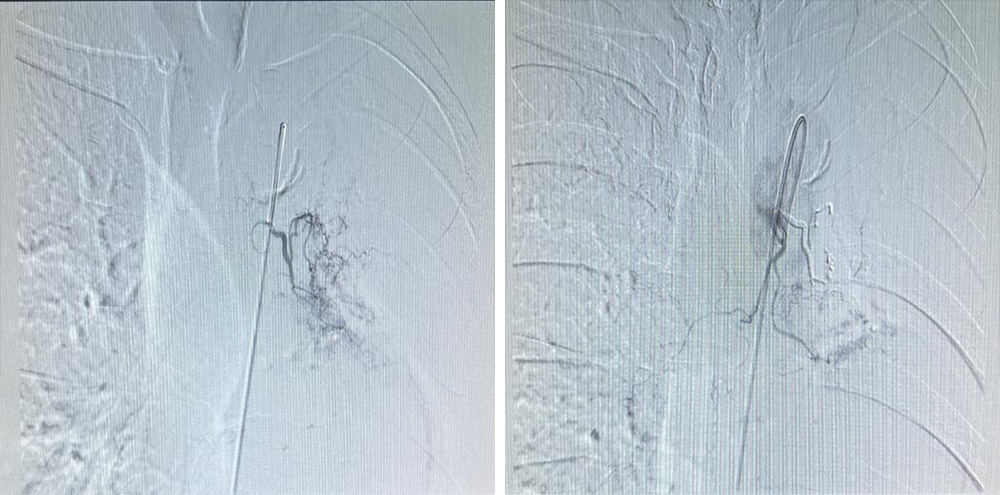

在气管分叉处主动脉偏左前壁找到左侧支气管动脉

经造影后可见造影剂异常外渗,明确出血靶血管

应用医用胶+明胶海绵颗粒行充分栓塞,栓塞后反复造影可见出血血管闭塞,异常染色消失,达到栓塞充分效果,患者无不良事件发生。